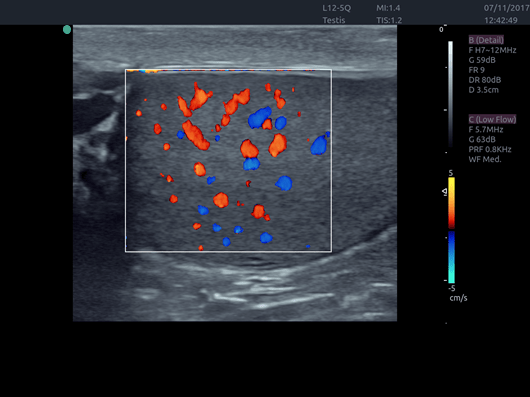

Invictus E5

O ultrassom Invictus E5 apresenta um design moderno e exclusivo, com perfeito fluxo de trabalho e interface intuitiva.

Dentre suas características inovadoras, podemos destacar a tela em LCD com rotação de 60° para ambos os lados, para otimização da visualização durante os exames; tela touch screen com menu totalmente customizável; painel de controle totalmente selado para facilitar limpeza e desinfecção da superfície, o que o torna referência para ser utilizado principalmente em Centro Cirúrgico.

Apresenta excelente qualidade de imagem, trabalho otimizado através de presets pré-determinados, sensibilidade e eficiência em aplicações de Point of Care e portanto, uma perfeita relação custo benefício.